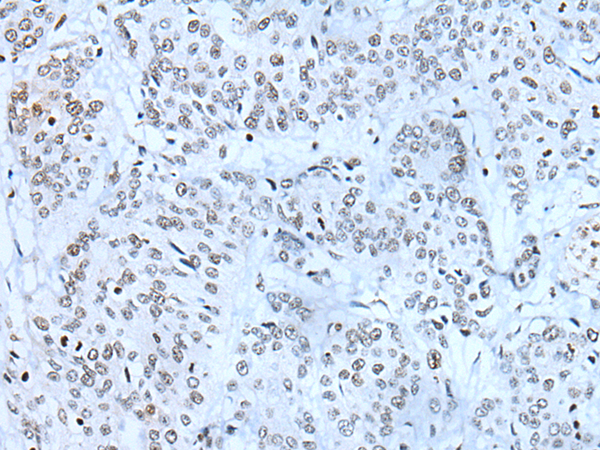

IHC positive control:

Human prostate cancer and human tonsil